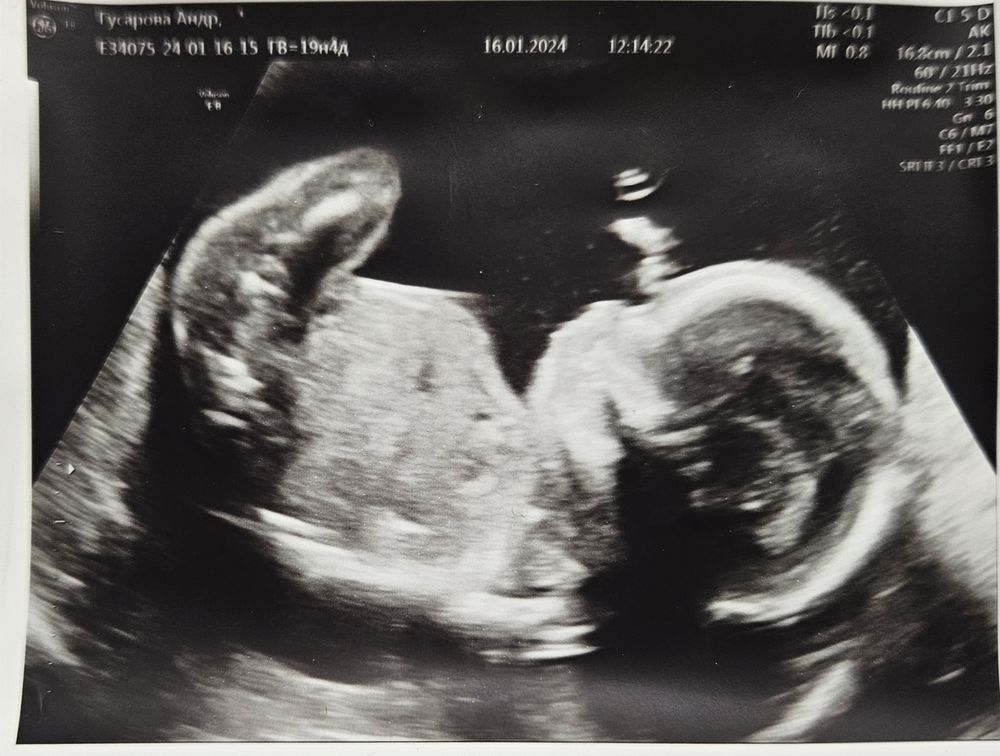

Второй скрининг. Экватор.

Изображение

Ну вот и настал мой личный экватор, 19.4 надели, полпути пройдено, так как кесарить будут в 38-39 недель.

Прошли 2 скрининг, всё хорошо с нашим мальч